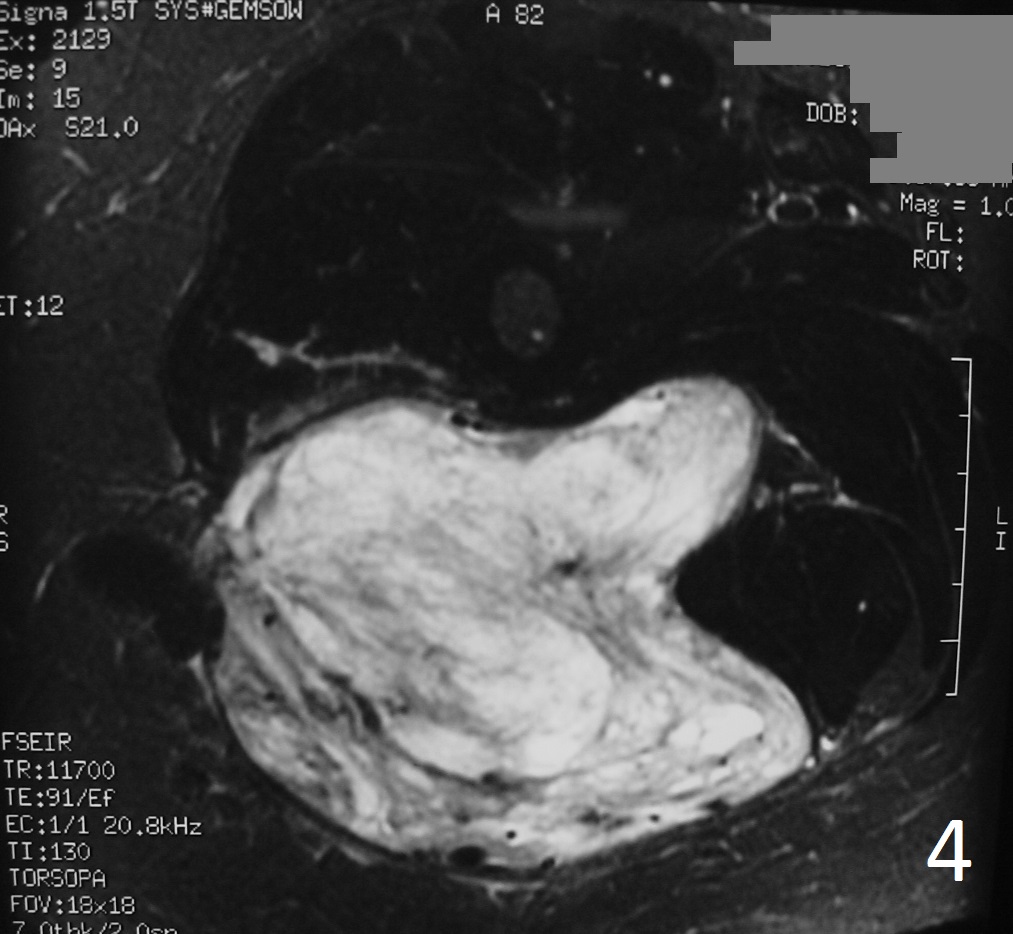

Fig 4-6: T2W FS demonstrates same features (Fig. 4) . Sagittal T1W (Fig. 5) and T1W FS (Fig. 6) of same case.